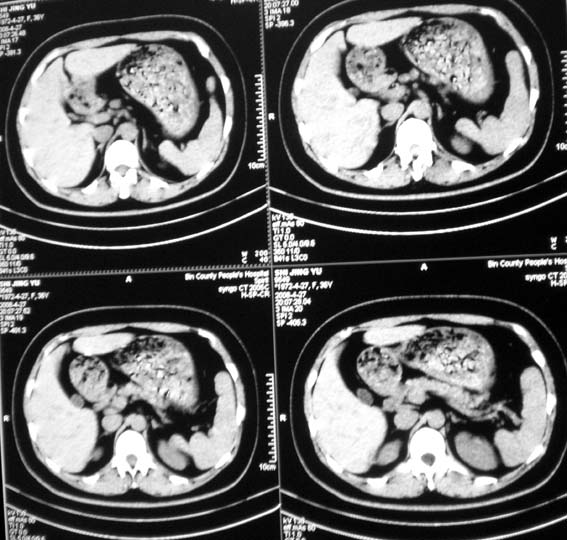

标题: CT13126:腰痛,肾区痛。

女,36岁,腰痛,肾区痛曾有肾囊肿史。

右肾有囊肿,余未件异常

髓质海绵肾?建议mr。